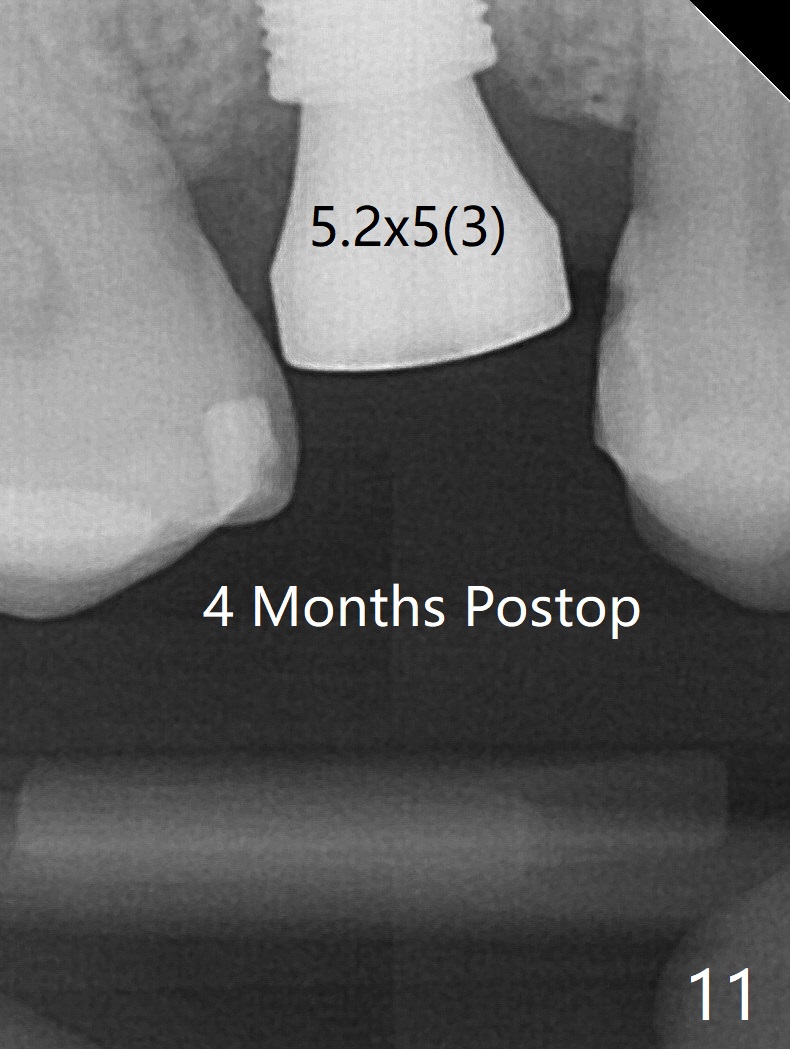

40岁女右上5近中龈下龋齿(图一),要求拔除植牙,上颌窦底板已经破坏穿孔,但是窦膜完整(图二)。清创后,放置PRF膜和粘性骨粉,用挖匙和上颌窦充填器尽量往上面推。然后放置导板,使用2.2x7.3 和3.0x7.3毫米钻头完成钻洞,可能无意中把骨粉推入上颌窦,之后利用报废植体(图三,四)完成提升,同时修补根尖缺损(利用之前放置的骨粉,图四:*,与图五(术前)对比)。当报废植体取出时,植牙窝已经形成,再放入少量骨粉,植入同样大小(之前扭力高)正式植体(不同品牌,图六,七),这时扭力低,放置愈合帽和骨粉(图七,八),以及6-9个月吸收膜,使用牙周胶水固定(图九),最后牙周敷料。术中术后几个小时没有上颌窦膜破裂迹象。术后一周牙周敷料松动,造成不适,去除时,膜好像粘附于敷料一起去除,骨粉暴露(图十),使用树脂敷料固定。后者术后一个月去除,因为局部有臭味。术后4个月切开放置愈合基台(图十一),术后五个月放置修复基台(图十二),使用塑料袖取模。术后5.5月同时放置牙冠和基台,十分顺手,口内粘固,之后同时取出,除去多余粘固剂,然后拧紧30Ncm(厂家推荐35 Ncm),一切非常顺利,觉得拍摄X光片是多余的。美中不足的是开孔(access hole)偏腭侧(图十二;由于自由手植入植体,与设计对比)。